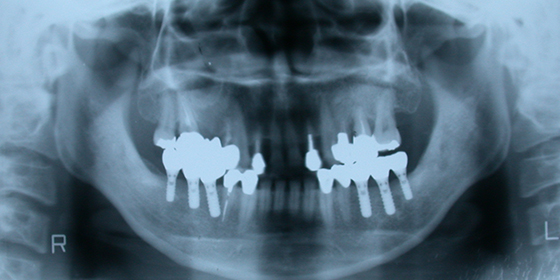

当院のインプラント治療例

術前

術後

当院でインプラントを埋め込んだ例(下顎)。